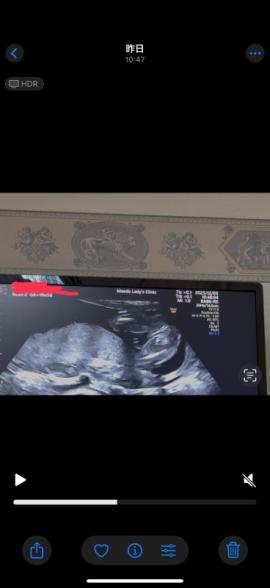

21週になりました!

ですが、まだ性別がわかりません。

いつもエコー見て検索魔になってしまい。

もし分かるのであれば教えて欲しいです

なので断言はできませんが、足と足の間男の子シンボルがはっきりと映っていなそうに感じたのと割れ目が見られるようにも思いましたので、女の子の可能性があるのではと思いました。

しかしはっきりとはわからないため、また次の健診の際に先生へご確認ください。